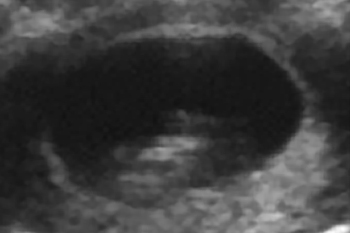

妊娠10週

子宮の中にいる赤ちゃんの超音波写真を見てみましょう。

妊娠中の子宮は、丸くて柔らかく赤ちゃんが心地よく過ごせる場所です。赤ちゃんは本来胎内を、膝を曲げ、指をなめられる姿勢で過ごします。

ところが、子宮まわりの筋肉がコリ固まってカチカチだったり内臓が下がって子宮が押しつぶされたりすると、子宮が細長い形になってしまいます。この中の赤ちゃんは窮屈で楽な姿勢をとることができません。